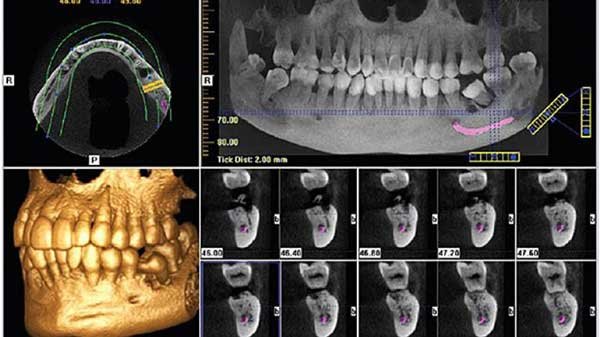

A CBCT, vagyis a háromdimenziós fogászati CT a legmodernebb diagnosztikai eszköz, amely lehetővé teszi a fogak, az állcsont, az ízületek és az arcüreg részletgazdag vizsgálatát. A felvétel háromdimenziós képet ad, így pontosabb információt nyújt, mint a hagyományos röntgenfelvételek.

Implantációs kezelések és csontpótlás előtt

Bonyolult gyökérkezelés vagy rezekció tervezésekor

Góckutatás esetén

Nehezen eltávolítható bölcsességfogaknál

Rejtett vagy visszamaradt fogak esetén

Arcüregközeli gyulladások, ciszta vagy elváltozás vizsgálatára

A vizsgálat gyors, fájdalommentes, beutaló nélkül elérhető, és bármely életkorban elvégezhető, amennyiben indokolt. A felvétel elkészítése előtt a páciensnek le kell vennie minden ékszert, szemüveget.

A CBCT-felvétel nálunk digitális formában vagy CD-n is kérhető, így könnyen megosztható más orvossal is.

A 3D CBCT (kúpsugaras CT) ezzel szemben háromdimenziós, nagy felbontású képet készít a csont- és fogstruktúrákról. Ez elengedhetetlen implantáció, gyökérkezelés, szájsebészet vagy góckutatás esetén, mivel pontosabb, rétegekre bontott információt ad.